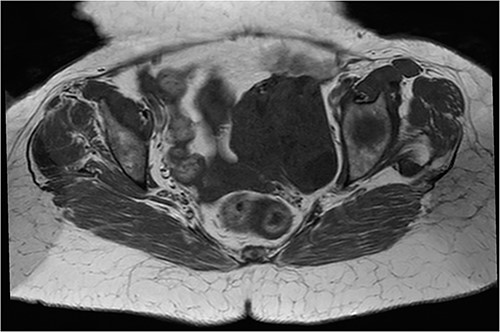

An abdomino-pelvic ultrasound was performed showing a pelvic lesional process with a left-lateralized supra uterin location, with a mixed echo-structure, mainly of tissue, classified O-RADS 5 (Figs 1 and 2).

Coronal T2 sequence: left uterine mass, heterogeneous, in T2 hyposignal containing areas in hypersignal.